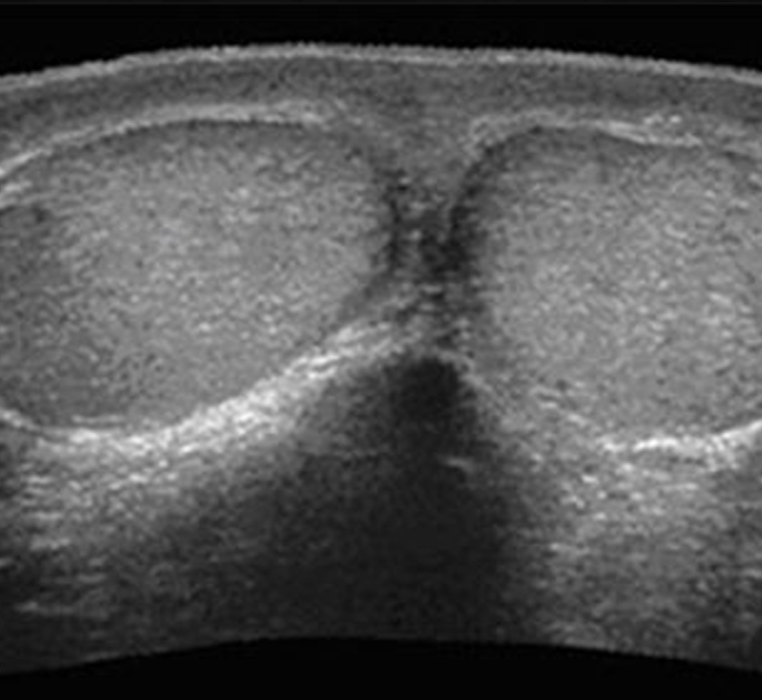

Ecografía Testicular